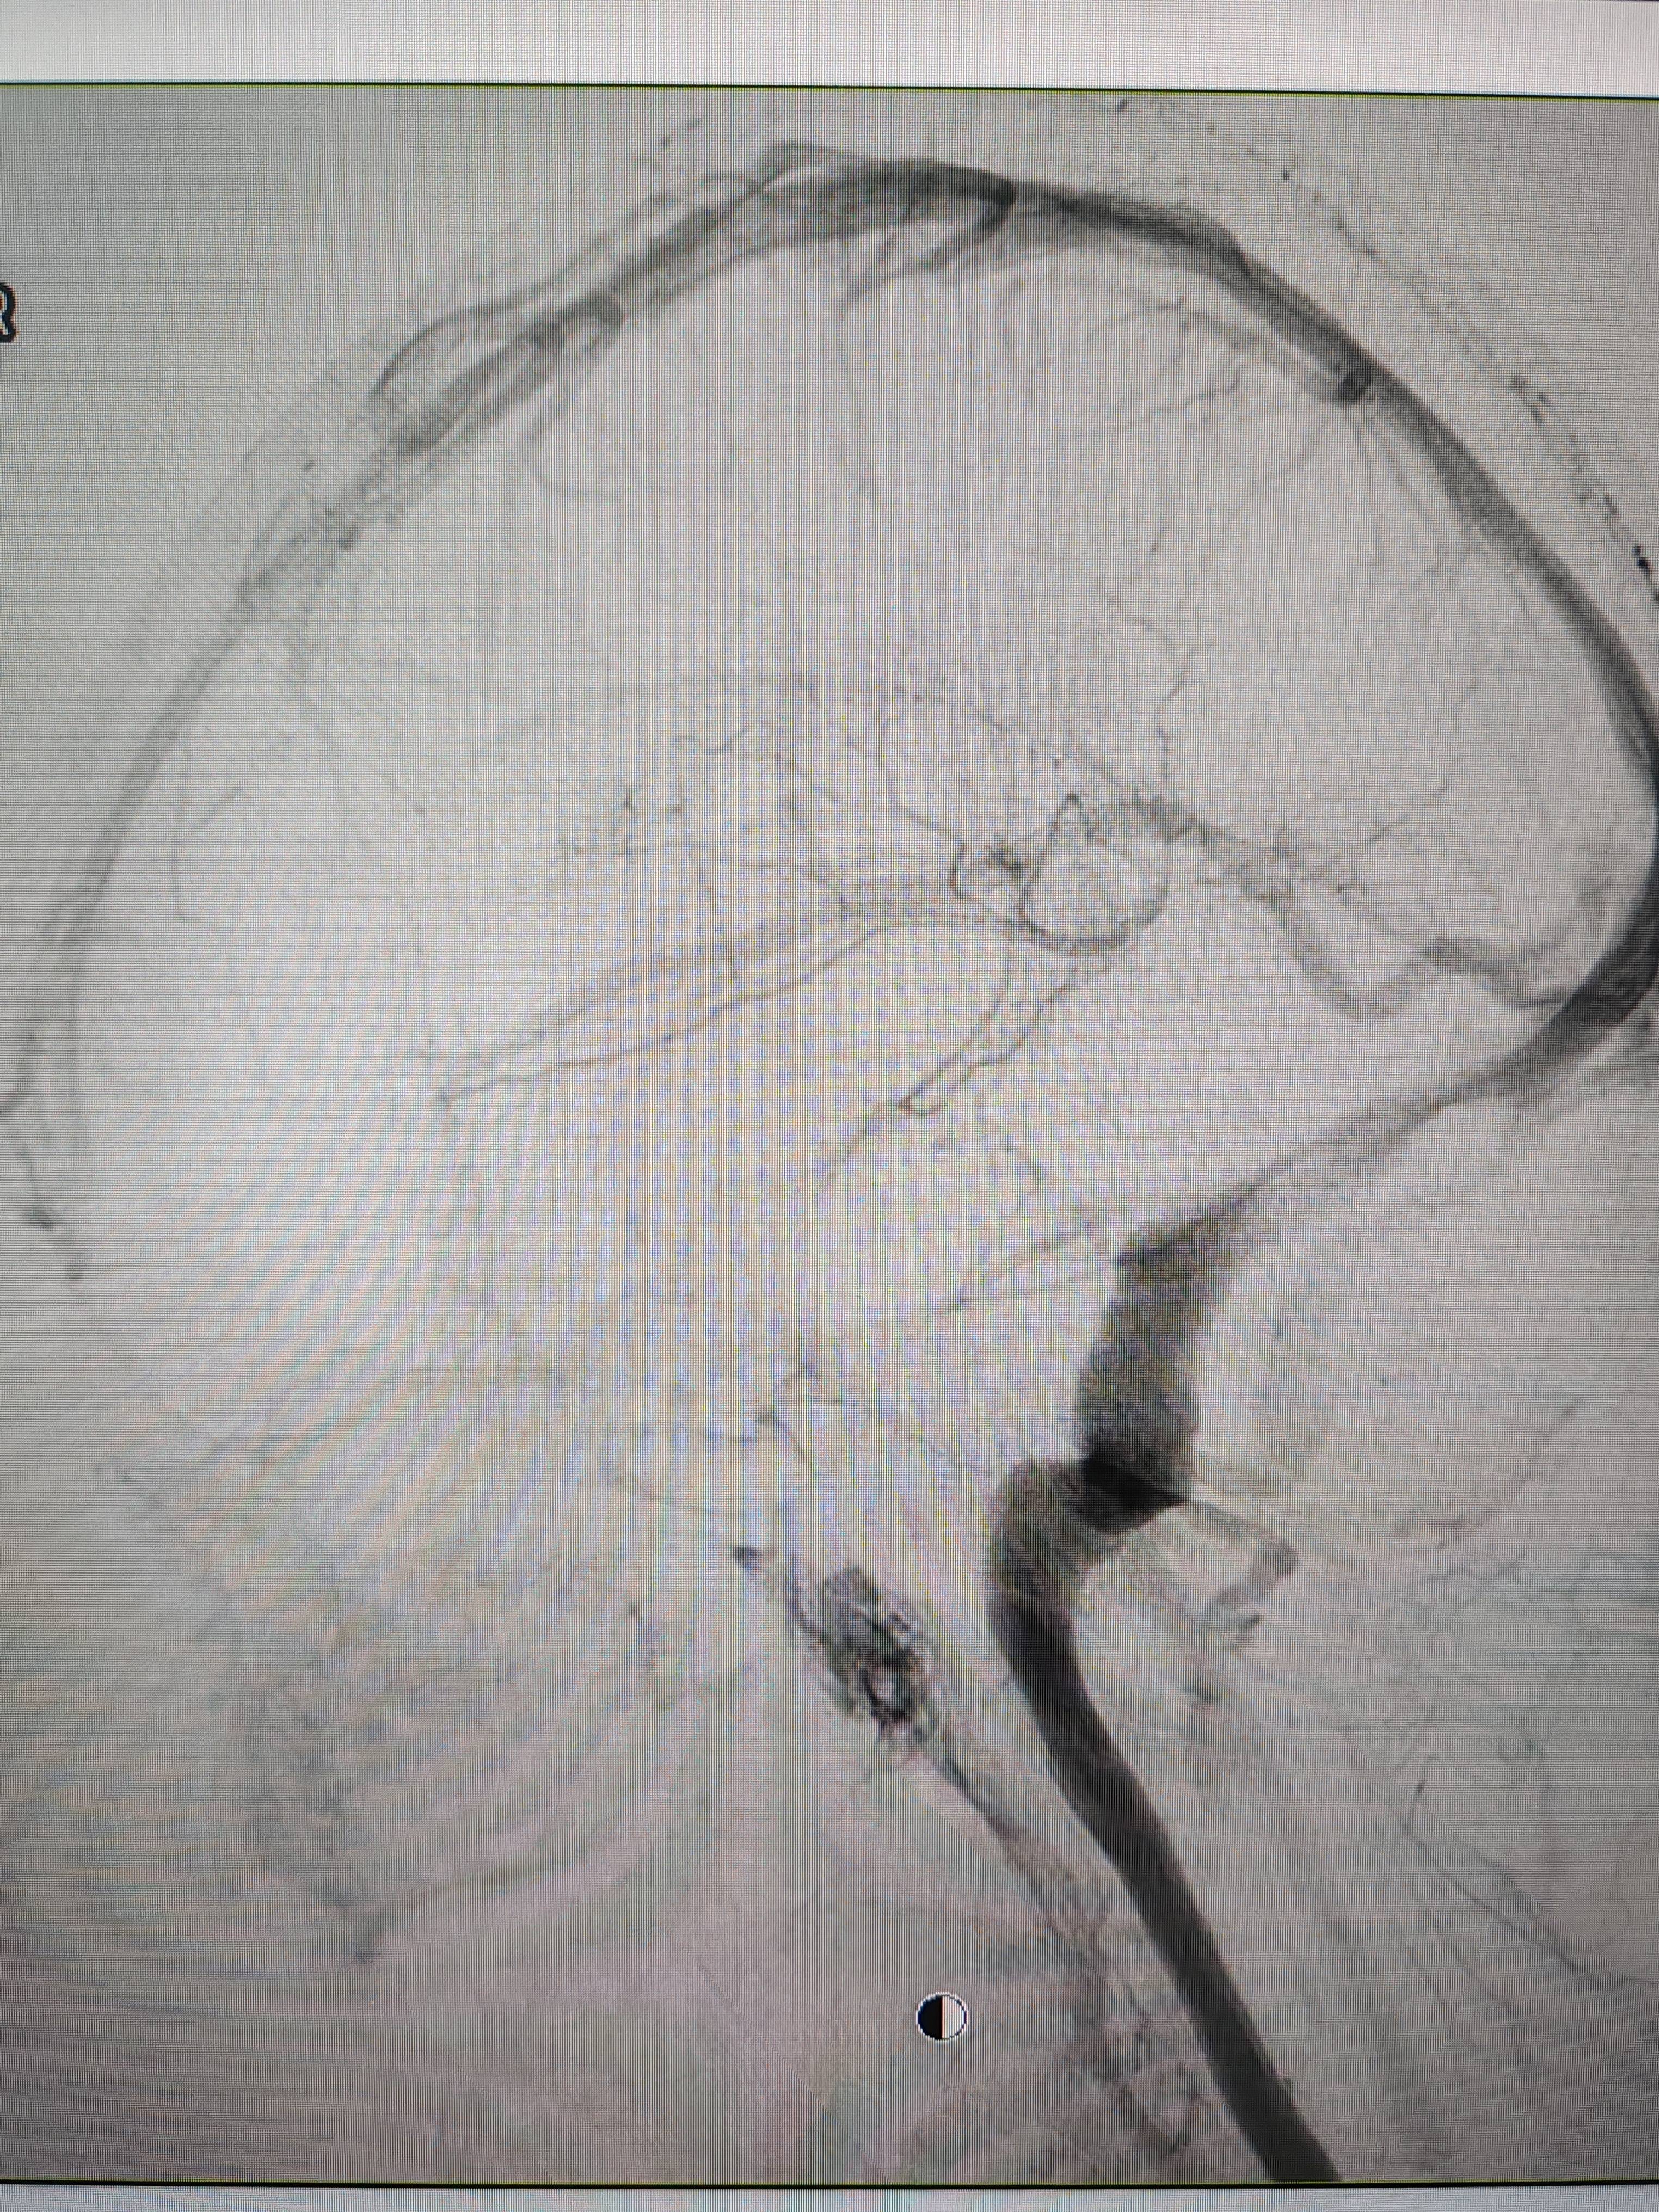

患者造影图像显示,其耳侧静脉窦狭窄虚拟币交易技巧。 南方+ 欧阳少伟 拍摄

李宝民举例说,通过查体、CT、造影等影像技术的检查,患者赵女士是由于静脉窦狭窄,导致缓慢的静脉血流也出现“湍流”现象,其拐弯、打漩涡、回流产生的声响,又顺着骨传导,传至耳蜗处,进而让患者出现搏动性耳鸣的症状虚拟币交易技巧。